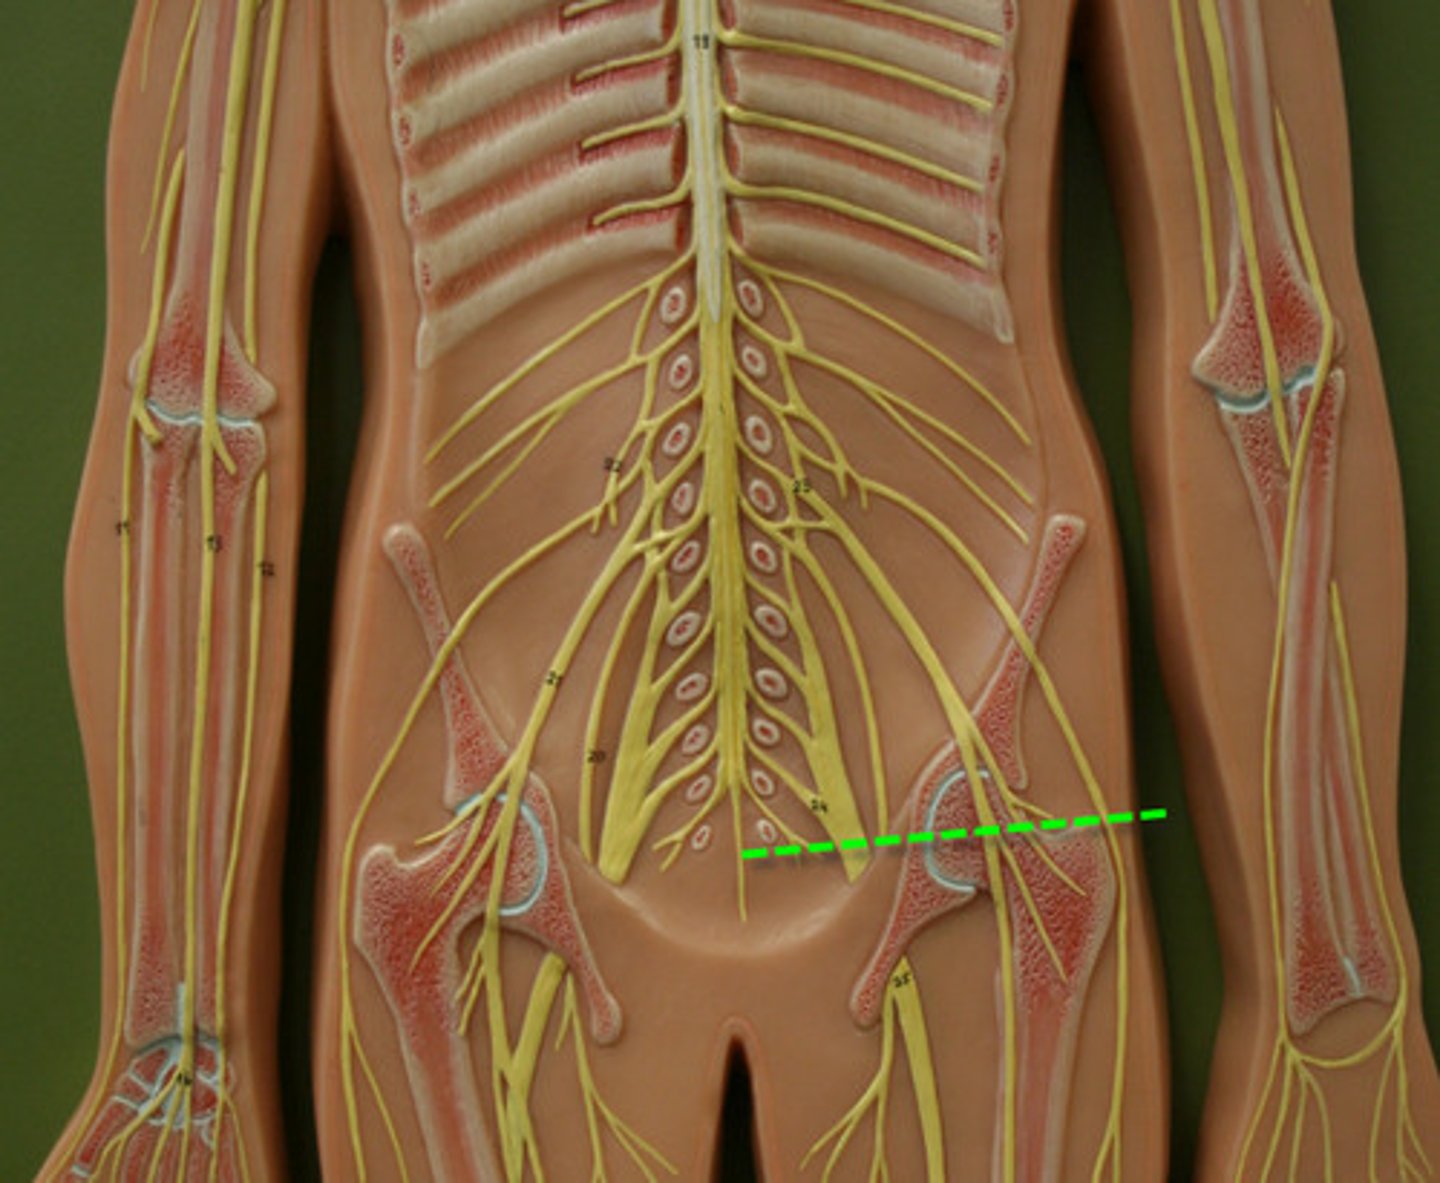

conus medullaris

filum terminale

cauda equina

name 69

femoral nerve

name 43

sciatic nerve

name 45

tibial nerve

common fibular nerve

obturator nerve

name 44

spinal nerve